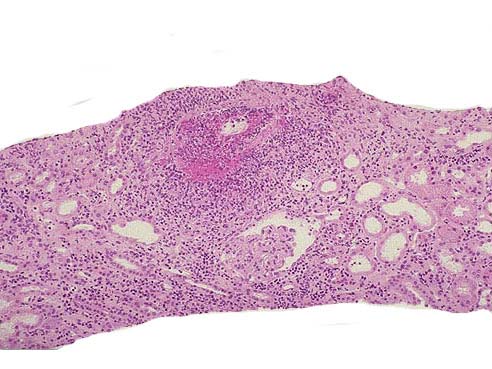

韦格氏肉芽肿患者病变部位镜下可出现如图所示改变,下列关于该病说法错误的是()。

[单选题]韦格氏肉芽肿患者病变部位镜下可出现如图所示改变,下列关于该病说法错误的是()A . 30~50岁多见,男性略多B . 在动脉壁、动脉周围或血管外部区域出现肉芽肿炎症C . 多数患者出现不同程度的肾小球肾炎D . 肾脏病变常为局灶坏死性肾小球肾炎伴新月体形成E . 严重者可引起急性肾功能衰竭